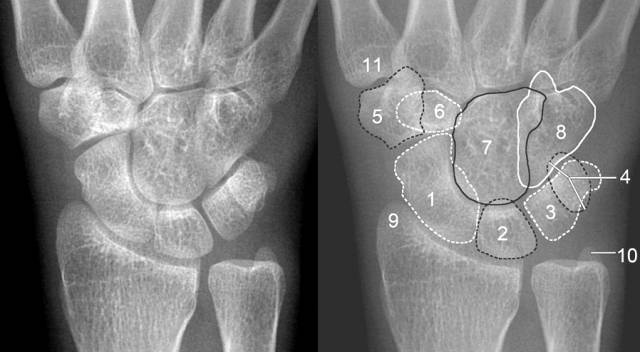

腕关节脱位及其x片阅读技巧

腕关节脱位及x线阅片技巧

腕关节脱位x线图片